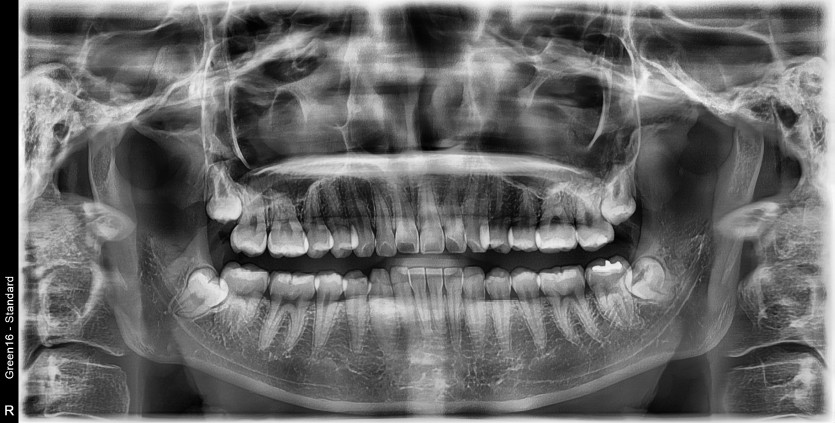

#38,48 사랑니 발치

구강 외과 전문의가 당일 발치했습니다.